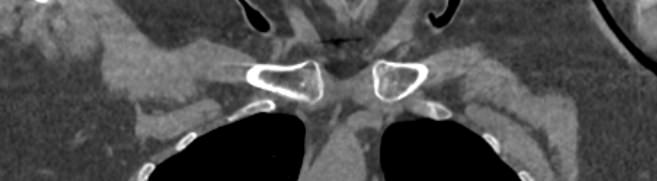

Наиболее информативным методом диагностики заболеваний ключицы является мультиспиральная компьютерная томография, которая наиболее часто применяется в ортопедии и травматологии. Метод основан на сканировании костей, суставов и внутренних органов при помощи веерообразного пучка рентгеновских лучей.

Источник рентгеновского излучения совершает непрерывное вращение вокруг объекта исследования и производит одномоментно множество послойных снимков, которые затем при помощи цифровой обработки данных преобразуются в трехмерные пространственные модели исследуемого органа.

В наших диагностических центрах обследование ключицы проводится на современном оборудовании экспертного класса. В клинике установлены новейшие мультиспиральные компьютерные томографы последнего поколения TOSHIBA AQUILION. Аппараты выполняют послойное сканирование исследуемой зоны с шагом от 0,5 мм, получая детальные снимки и трехмерные изображения высокого качества. При этом возможности аппаратов обеспечивают пониженный уровень лучевой нагрузки на пациента.